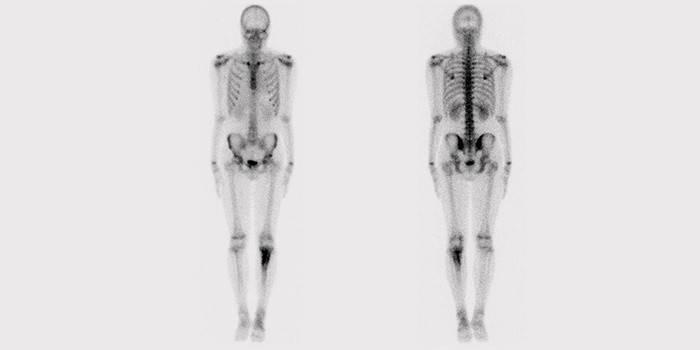

Scyntygrafia kości szkieletowej

Procedura badania kości i tkanek szkieletowych na podstawie promieniowania radioizotopowego pozwoli ocenić stan narządów pod kątem odpowiedniego leczenia. Ta metoda wizualizacji funkcjonalnej przeprowadzana jest w specjalnej kamerze gamma. Lekarze twierdzą, że osteoscyntygrafia przewyższa standardową radiografię pod względem skuteczności.

Jest to innowacyjna diagnoza radiacyjna, która może określić aktualny stan narządów i integralność struktury tkanek ciała. Procedura pomoże zidentyfikować nowotwory złośliwe w komórkach, a także zmiany w kościach na najwcześniejszych etapach (przed pojawieniem się zewnętrznych oznak). Zastosowanie scyntygrafii kości szkieletowych ujawni wszystkie problemy związane z występowaniem wszelkiego rodzaju dolegliwości tkankowych, co przyczynia się do wyznaczenia terminowej i odpowiedniej terapii.

Aby uzyskać prawidłowy obraz badania, radionuklidy są wprowadzane do organizmu - specjalne markery (środki kontrastowe), których promieniowanie jest wyświetlane na ekranie kamery gamma. Z tego powodu wszystkie uszkodzone i dotknięte tkanki stają się widoczne. Wskaźniki pojawiają się na monitorze jako punkty aktywne. Te miejsca to zmiany. Izotopy promieniotwórcze są praktycznie nieszkodliwe dla organizmu, co czyni procedurę bezpieczną i niezwykle popularną.

- Następnie wykonuje się zdjęcie kości szkieletu na specjalnym aparacie składającym się z kamery gamma i stołu zabiegowego. Skanowanie zajmuje około godziny, a pacjent musi cały czas spędzać bez ruchu. Podczas scyntygrafii aparat znajduje uszkodzone części szkieletu z powodu lokalizacji w nich wskaźników radioaktywnych (gorące ogniska).